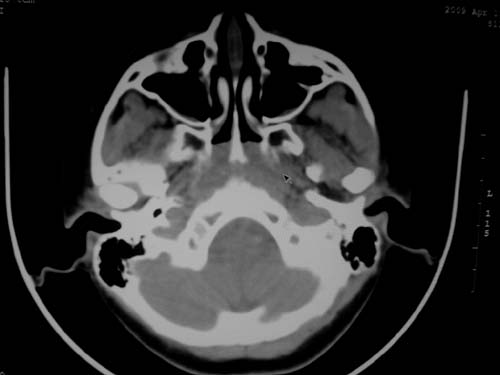

标题: CT19740:女,12岁,鼻塞,流黄鼻涕。 [打印本页]

标题: CT19740:女,12岁,鼻塞,流黄鼻涕。

双侧上颌窦炎,增殖腺肥大。

1)双侧上颌窦炎。2)鼻咽腺样体肥大。